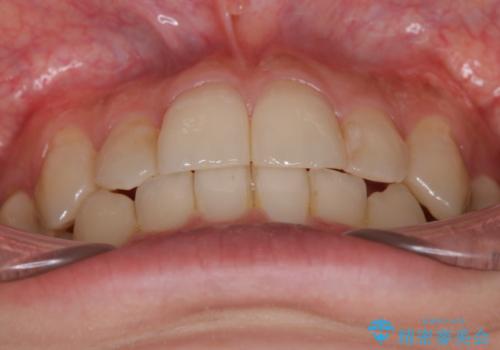

奥歯を後方に移動することで、歯を抜かずに矯正を終えることができました。